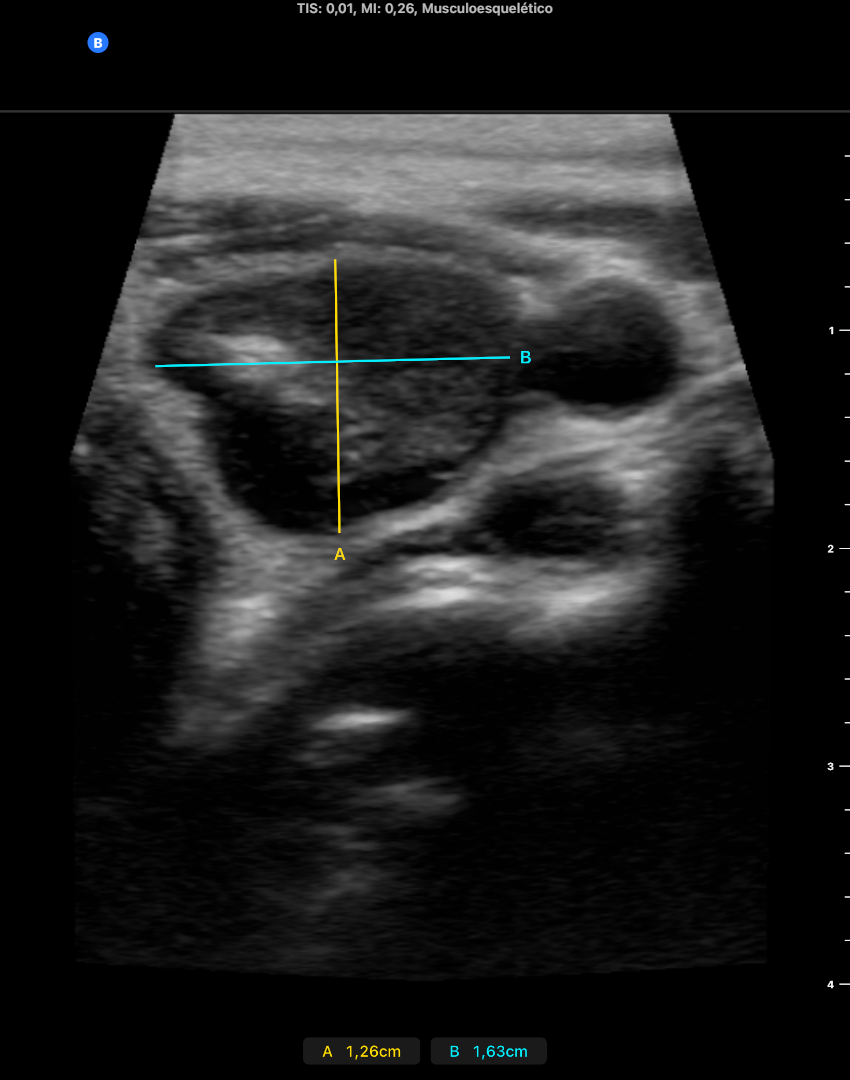

En LTD se objetivan 2 nódulos, uno de ellos quistico y el otro solido bien delimitados, que no captan doppler de 2 x 3 x 2 mm cada uno aproximdamente en diametros APxTxL.

En LTI se objetiva un nódulo predominante de 30 mm de diámetro L y 16 x 14 mm en diámetros APxT captante de Doppler, de contenido casi solido, TIRADS 4-5. No adenopatias laterocervicales sospechosas.